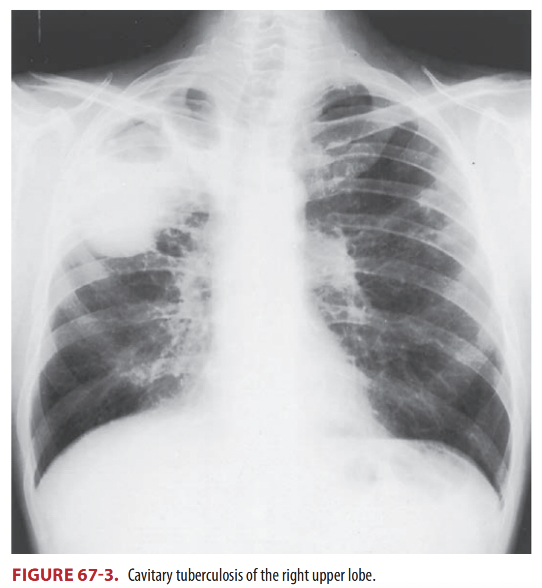

Remarks on cavitary pulmonary tuberculosis

A

1. Patients with cavity have a bacterial load of up to 10^11 bacilli/gram, making it highly contagious. (Lond, 2012)

2. Start or maintain therapy while awaiting smear and culture results on all patients with suspicious findings of active tuberculosis, notably cavitary lesions or known previous infecdtion with new weakness or fevers

3. Use prolonged therapy in immunocompromised patients, patients with cavitary pulmonary tuberculosis and positive sputum culture after 2 months of therapy

4. The yield of sputum smears and cultures is lower in children because of difficulty in obtaining adequate samples in addition to lower incidence of cavitary disease